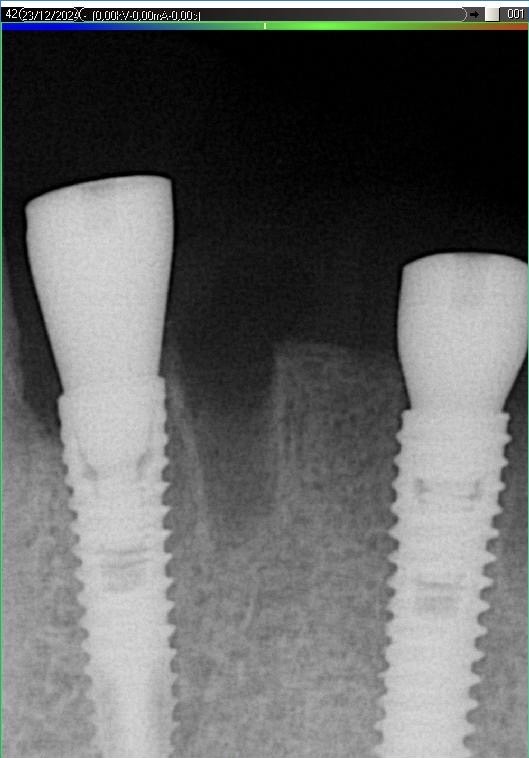

Імплантація